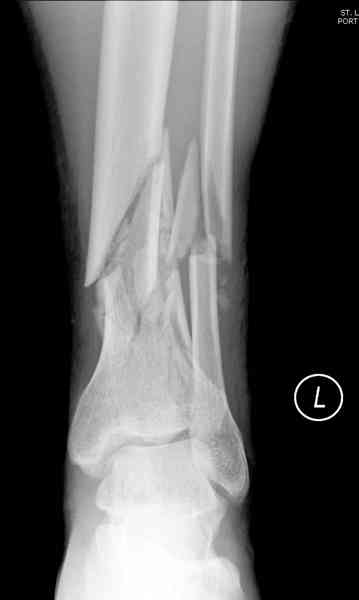

При высокоскоростных переломах редко можно встретить изолированную травму пилона, и в моей практике изолированные травмы большая редкость, поэтому, как дополнение к обсуждаемой теме, решил представить свежий, двухдневной давности случай.

Предыдущей сменой до 4:00 утра по поводу открытого перелома бедра, тибиал плато, пилон и надколенника сделана операция.

Пострадавшему 21 г., травма скоростная, после I&D с расширением раны, на бедре сделана операция ретроградным интрамедуллярным штифтом, остеосинтез с частичной резекцией надколенника и ушивание собственной связки.

На голень наружный фиксатор, рану на бедре ушили (рана была изнутри кнаружи всего 2 см). По протоколу травматических больных, до операции обследован ангиографически, (у больного дистально не смогли определить пульсацию) сосудистый хирург подтвердил проходимость на всем протяжении магистрального сосуда нижней конечности по снимкам ангиограмм.